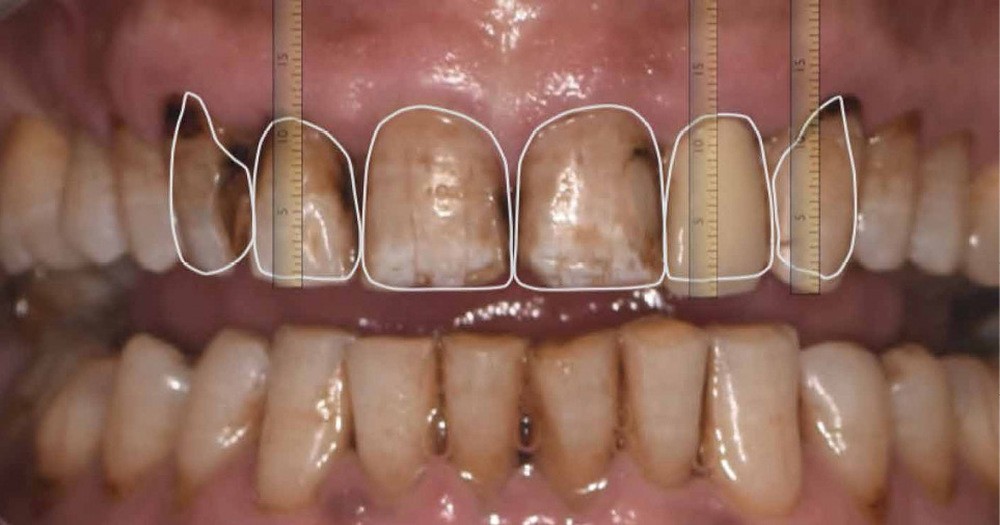

Un patient, âgé de 62 ans, nous consulte pour la réhabilitation de son sourire qu’il trouve disgracieux. Il est gêné par la longueur et l’aspect opaque de son incisive latérale supérieure gauche et, de manière générale, par la couleur et les fêlures présentes sur ses dents antérieures maxillaires.

On note la présence d’anciennes restaurations composites, de lésions carieuses actives et de pertes de substances amélo-dentinaires (fig. 1).

La première étape prothétique consiste en la réalisation de photographies intra/exo buccale et d’une empreinte numérique initiale. Cela permettra la réalisation d’une analyse esthétique (fig. 2) par la technique du Digital Smile Design (DSD) dans l’objectif :